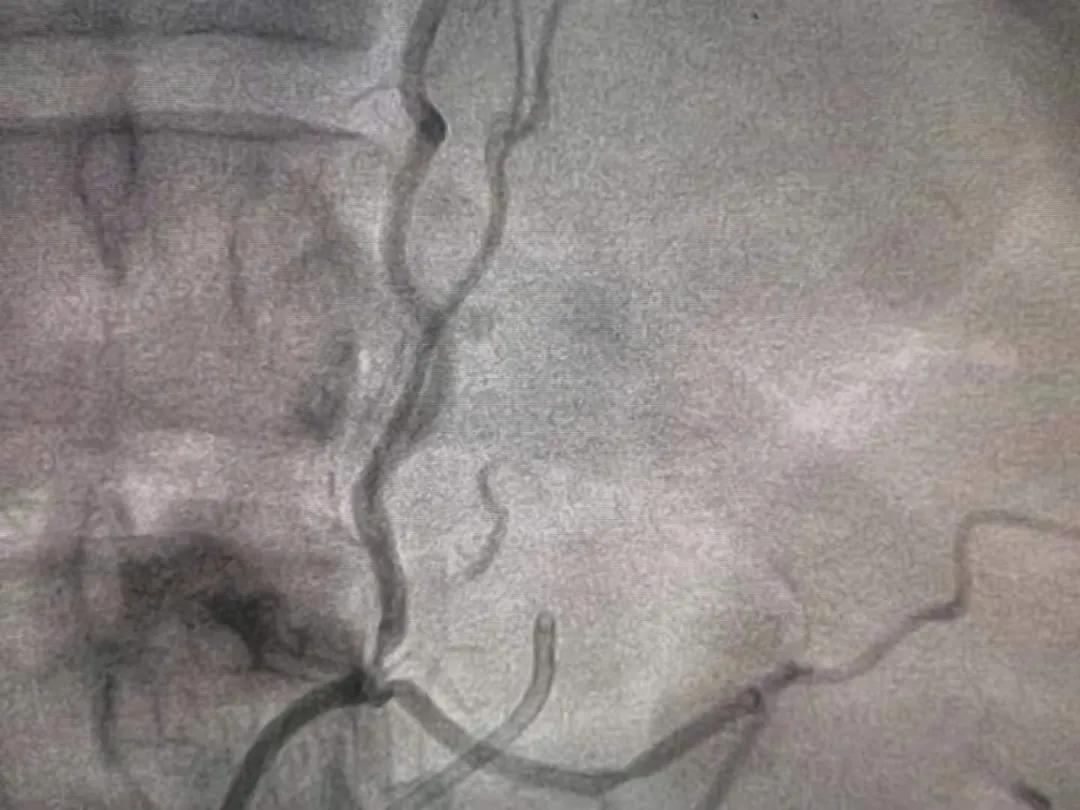

肾上腺动脉消融前

但这类对症治疗只能暂时控制住黄先生的病情,要想从根本上解决这个“病”还需另想办法。当得知医院心血管内科目前已开展针对该病的肾上腺动脉消融手术后,黄先生及其家属迅速向心血管内科主任王沛坚教授进行了咨询,并决定接受手术。

由于患者病情较为特殊,王沛坚教授亲自为黄先生进行了手术,手术历时1小时。

肾上腺动脉消融后

“原发性醛固酮增多症是最常见的继发性高血压类型之一,肾上腺动脉消融主要是针对原发性醛固酮增多症。术后结果相当理想,患者不但醛固酮、肾素、血钾均恢复到正常水平,下肢无力、麻木等症状消失,而且在服用小剂量降压药物的情况下血压在110-120mmHg左右,完全可以停用降压药物。”据王沛坚教授介绍。